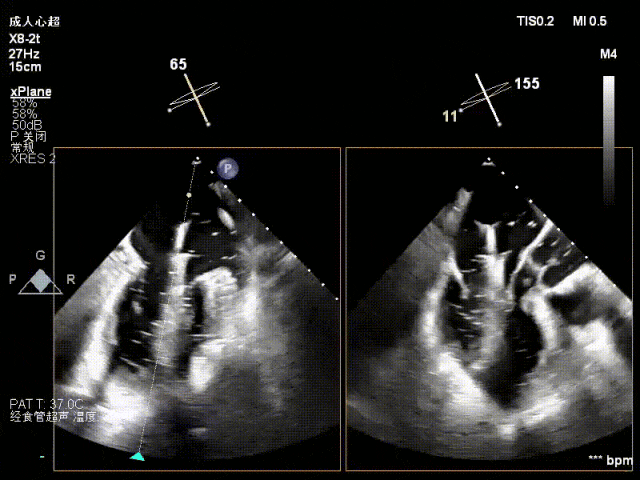

术中超声(关键步骤)

混合性MR,P2脱垂连枷(脱垂范围15mm,连枷间距4mm),腱索断裂

新分型:ACA型,反流2区及两侧,MR 4+,VC:3×14mm

A2:24mm,P2:17mm,AP:38mm,MVA约5.7cm²

术后,出院检查报告显示夹子位置固定,无移位,二尖瓣轻度反流,左室大小和LVEF值正常范围,左室壁运动分析未见明显异常。术后两个月随访检查,状态稳定,夹子位置固定,二尖瓣轻度反流,左室大小和LVEF值正常范围,左室壁运动分析未见明显异常(左室壁运动记分指数1分)。